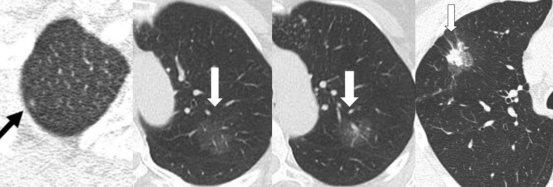

磨玻璃结节(GGN)是胸部CT上常见的影像学表现,因其与早期肺癌的关系而备受关注。近日,一项发表在《放射学》杂志的研究,通过对10年随访数据的分析,为磨玻璃结节的临床管理提供了重要参考。

1. CT随访是安全的:在磨玻璃结节出现实性成分前,CT随访是安全且合理的管理策略。

2. 避免不必要的手术:随访期间结节稳定或增大的患者,其预后与手术患者相当,因此无需过早手术。

3. 关注实性成分:一旦磨玻璃结节出现实性成分,应考虑手术干预。